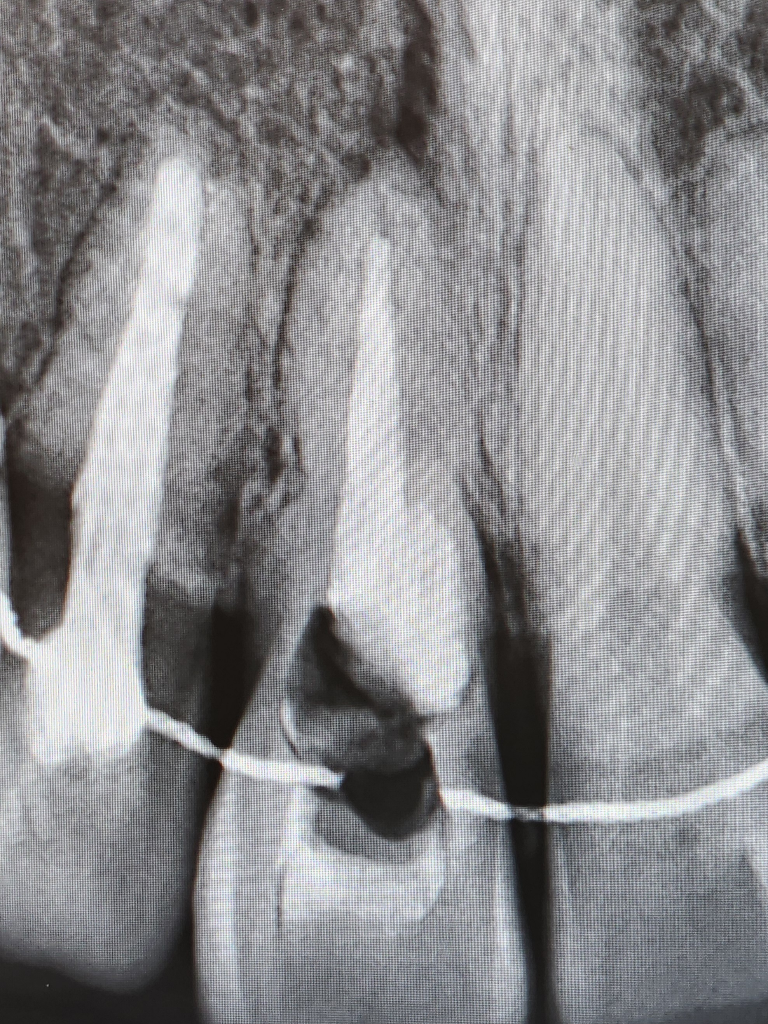

그래서 신경치료했던것을 다 긁어낸 후 다시 신경치료하고 그 이후 실활치미백을 진행했고, 9월-10월 사이 3번의 미백치료로 밝아진 줄 알았으나 12월쯤 다시 어두워지기 시작해 한번 더 받아 총 4번의 미백을 진행했습니다.

상담해주실때, 지금 이정도로 뚫어서 진행을 했었고, 아직도 안쪽에 사진상 보이는 저 검은색 부분이 오염된 부분이며 치아 안쪽을 더 뚫어서 다 제거하기에는 치아 외벽이 거의 남아있지 않아 치아 자체가 부서질 수 있다고 하셨습니다.

치아 뿌리끝에도 염증이 잇는거 같습니다. 소견서를 받아서 대학병원 보존과를 가셔서 검진을 받아보시는게 좋을것같습니다.